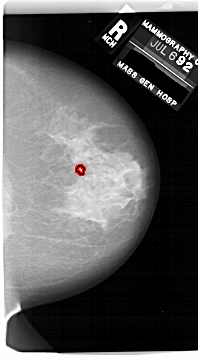

A_1749_1.RIGHT_MLO

RIGHT_MLO LINES 6616 PIXELS_PER_LINE 3631 BITS_PER_PIXEL 12 RESOLUTION 43.5 OVERLAY

FILE: A_1749_1.RIGHT_MLO.OVERLAY

TOTAL_ABNORMALITIES 1

ABNORMALITY 1

LESION_TYPE CALCIFICATION TYPE PLEOMORPHIC DISTRIBUTION CLUSTERED

ASSESSMENT 4

SUBTLETY 4

PATHOLOGY BENIGN

TOTAL_OUTLINES 1

BOUNDARY